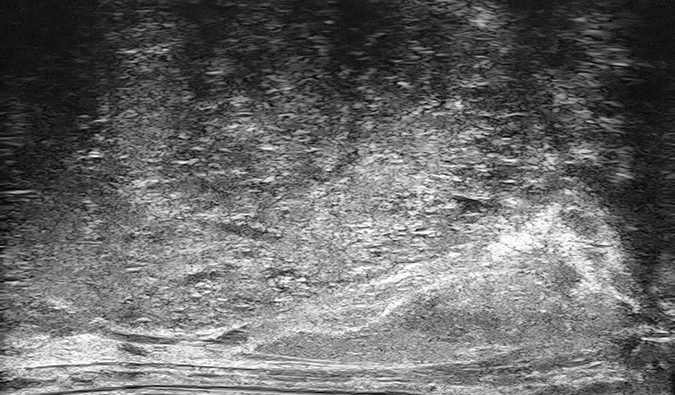

PRI-MUS 3

Mild heterogeneity or Bright Echoes in hyperechoic tissue